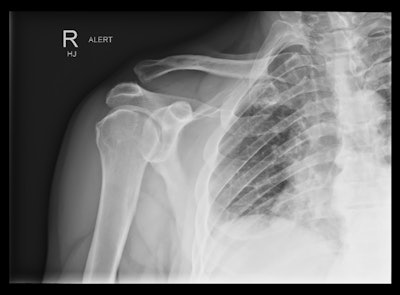

Acromioclavicular dislocation in suspected shoulder dislocation.